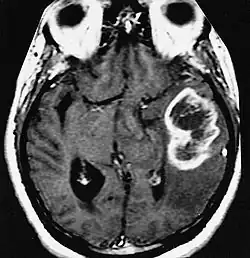

| An example of a ring-enhancement around a lesion in gliobastoma. In tumefactive multiple sclerosis, the ring-enhancement is open, not forming a complete ring. |

These atypical lesion characteristics include a large intracranial lesion of size greater than 2.0 cm with a mass effect, edema and an open ring enhancement. A mass effect is the effect of a mass on its surroundings, for example, exerting pressure on the surrounding brain matter. Edema is the build-up of fluid within the brain tissue. Usually, the ring enhancement is directed toward the cortical surface.[2] The tumefactive lesion may mimic a malignant glioma or cerebral abscess causing complications during the diagnosis of tumefactive MS. T2-hypointense rim and incomplete ring enhancement of the lesions on post-gadolinium T1- weighted imaging on brain MRI enable accurate diagnosis of TDL[3]

Diagnosis of tumefactive MS is commonly carried out using magnetic resonance imaging (MRI) and proton MR spectroscopy (H-MRS). Diagnosis is difficult as tumefactive MS may mimic the clinical and MRI characteristics of a glioma or a cerebral abscess. However, as compared to tumors and abscesses, tumefactive lesions have an open-ring enhancement as opposed to a complete ring enhancement.[1] Even with this information, multiple imaging technologies have to be used together with biochemical tests for accurate diagnosis of tumefactive MS.[36]

MRI diagnosis is based on lesions that are disseminated in time and space, meaning that there are multiple episodes and consisting of more than one area.[39] There are two kinds of MRI used in the diagnosis of tumefactive MS, T1-weighted imaging and T2-weighted imaging. Using T1-weighted imaging, the lesions are displayed with low signal intensity, meaning that the lesions appear darker than the rest of the brain. Using T2-weighted imaging, the lesions appear with high signal intensity, meaning that the lesions appear white and brighter than the rest of the brain. When T1-weighted imaging is contrast-enhanced through the addition of gadolinium, the open ring enhancement can be viewed as a white ring around the lesion.[40] A more specific MRI, Fluid attenuation inversion recovery (FLAIR) MRI show the signal intensity of the brain. Subjects with tumefactive multiple sclerosis may see a reduction of diffusion of the white matter in the affected area of the brain.[11]